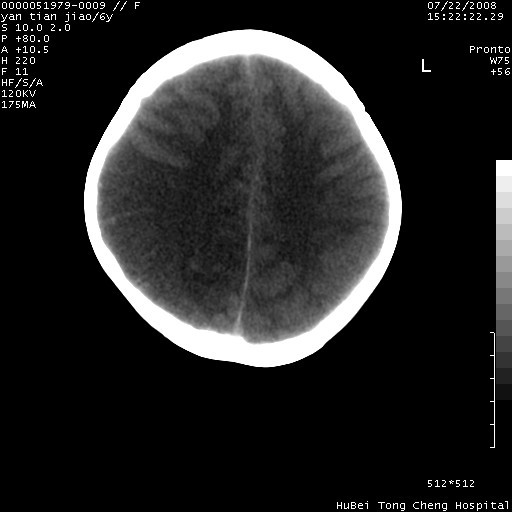

患儿 女,6岁。发热三天,昏迷五小时伴抽搐一次入院。pe:神志不清,浅昏迷状,双侧瞳孔不等大(右侧瞳孔直径3.5mm,左侧瞳孔2.0mm),对光反射迟钝,项强约一指,脑膜刺激征及病理反射阳性;双肺可及痰鸣音;四肢肌张力不高。

临床诊断:病毒性脑膜脑炎并脑疝?

颅脑ct轴位平扫,如下图:

大面积低密度区,可疑脑炎,建议强化!

结合临床症状,符合右颞顶枕叶病毒性脑膜脑炎.建议增强或mri。

右侧低密度区结合临床考虑脑炎